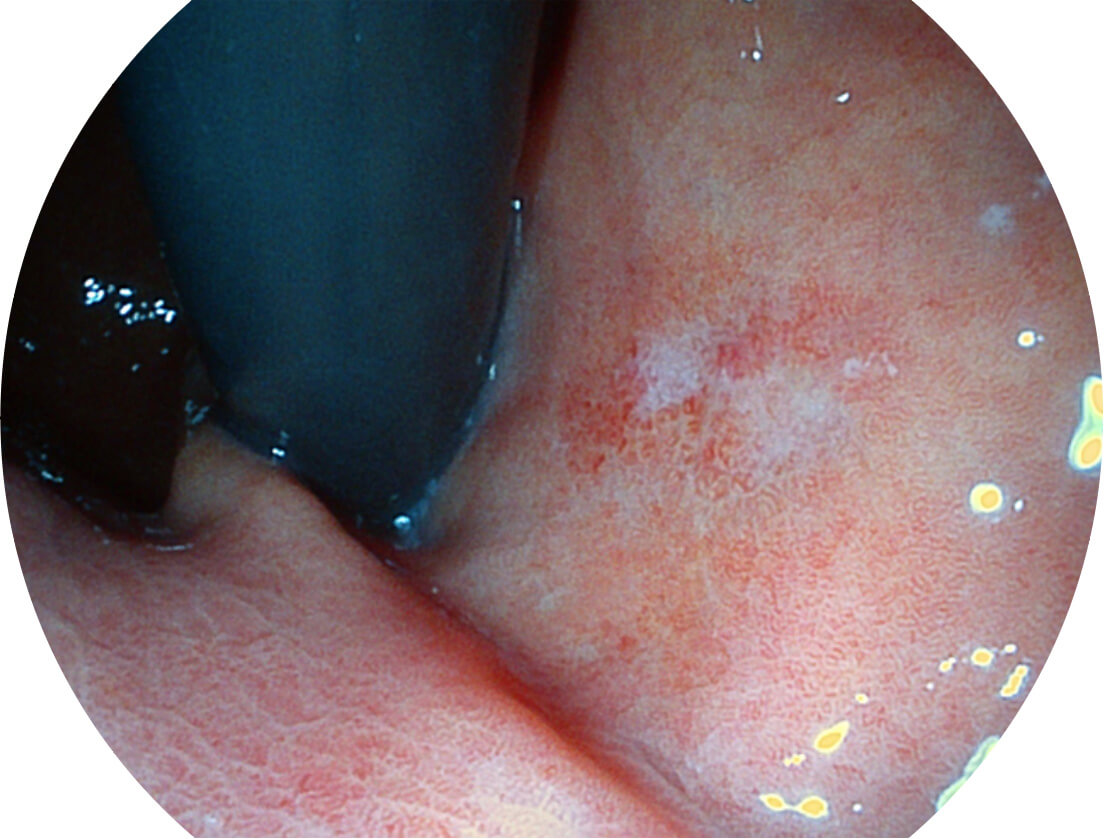

白光图像

SFI图像